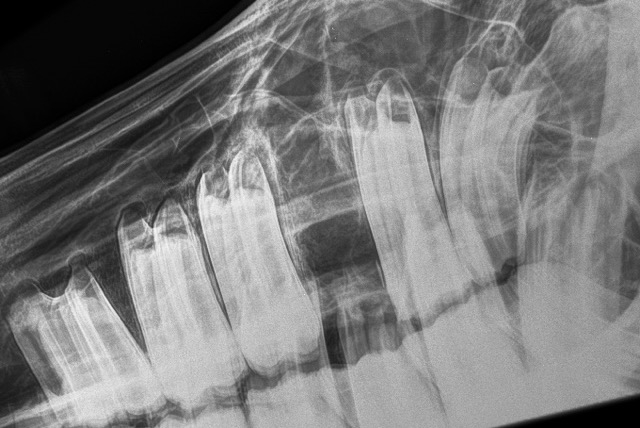

Radiograph of a head taken after extraction of a cheek tooth.